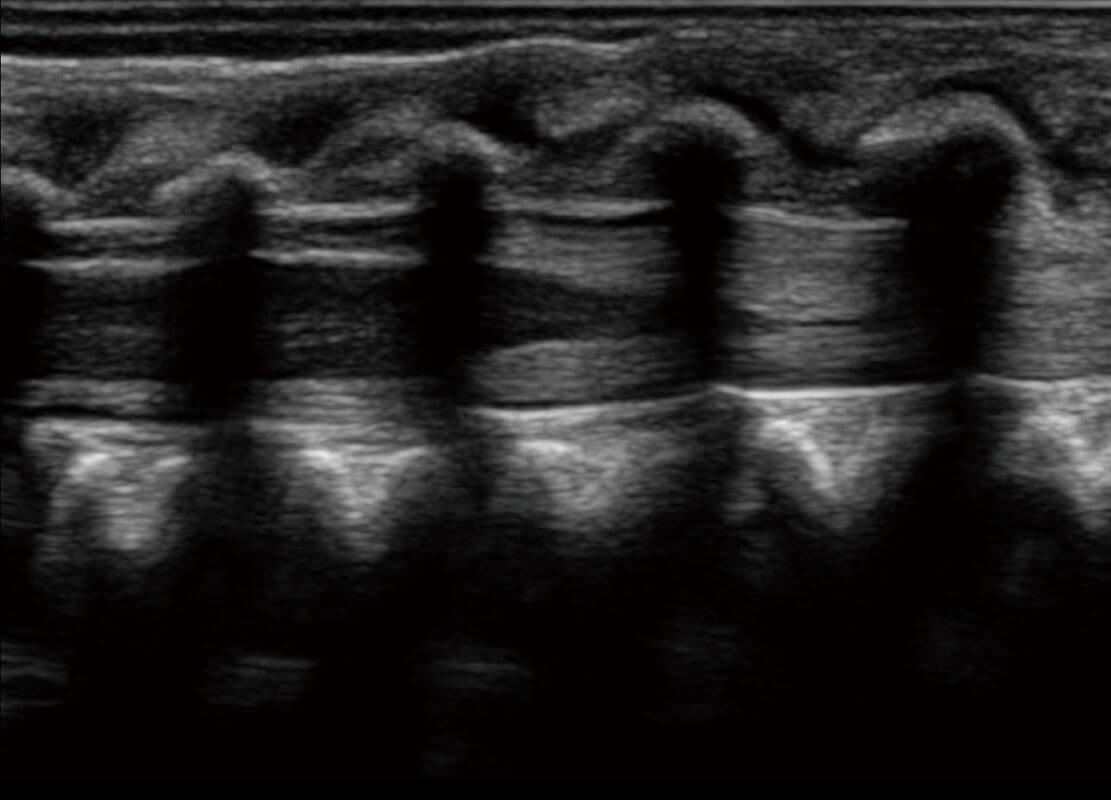

P60搭載寬頻帶線陣探頭、寬景成像、彈性成像技術(shù),為您提供乳腺應(yīng)用方案。P60支持高頻相控陣探頭、線陣探頭、腹部高頻探頭、腹部微凸探頭等,豐富的探頭群搭載敏感的彩色血流成像,適用于新生兒多種臟器檢測(cè)要求,滿足新生兒篩查需求。

新生兒心臟